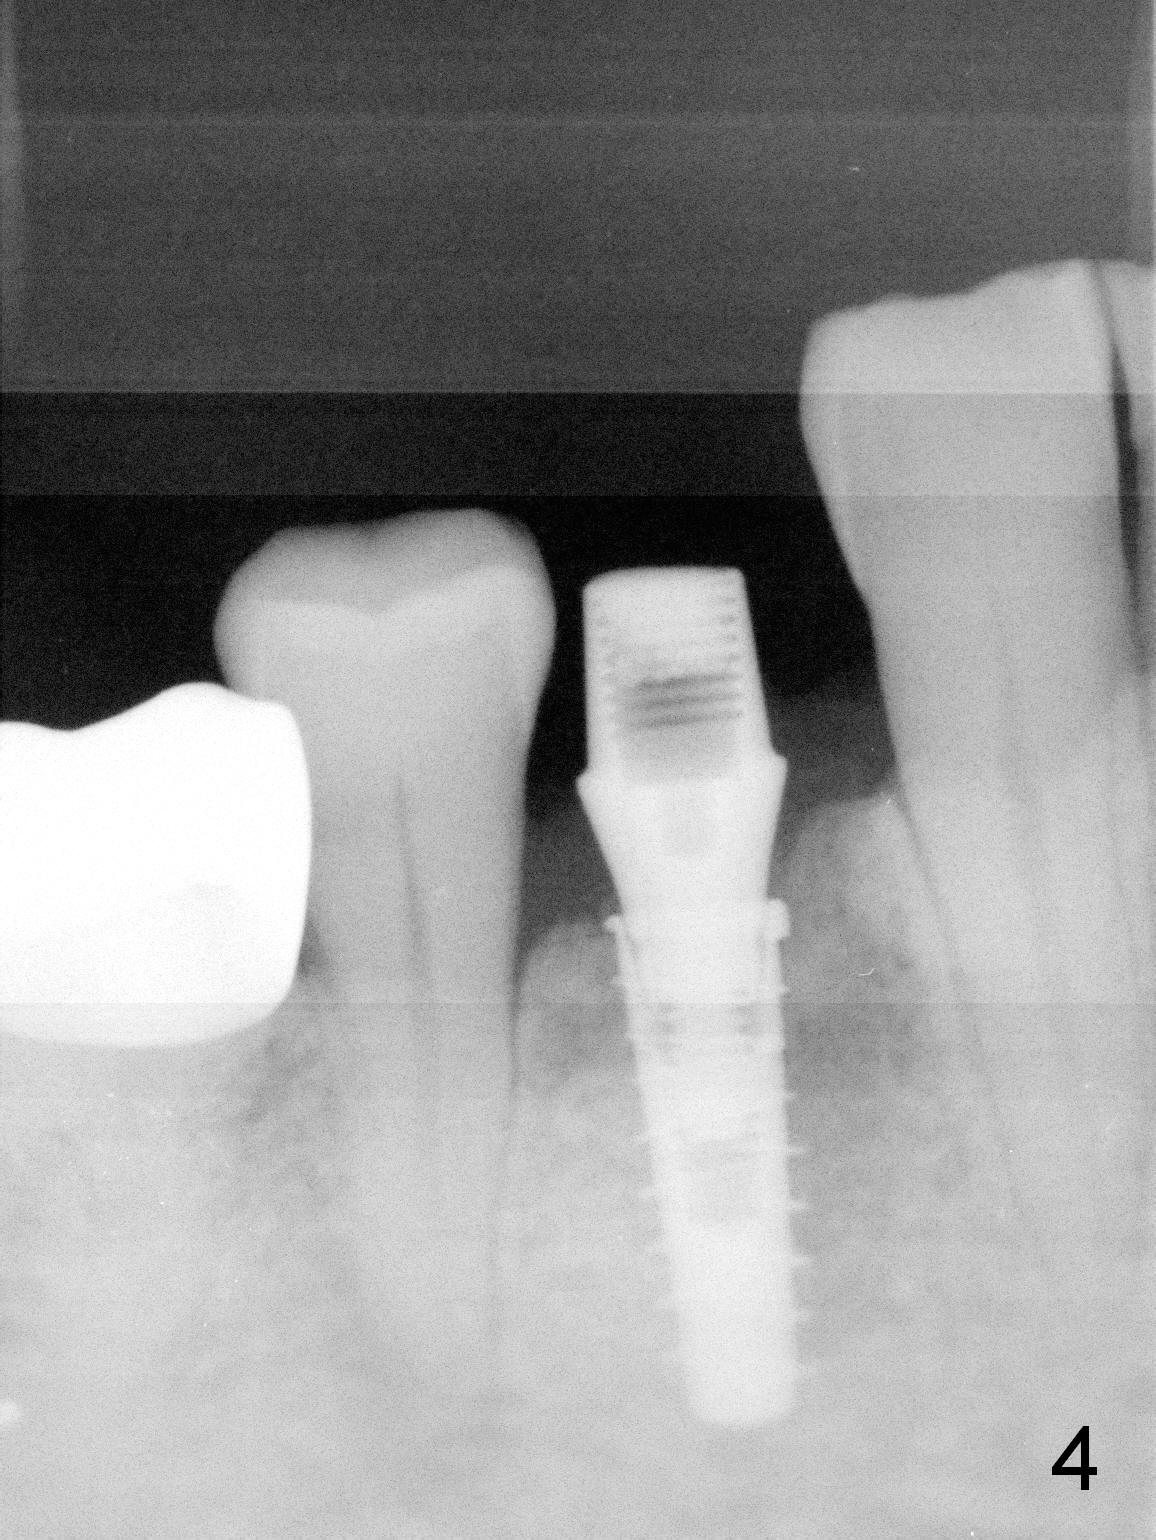

In fact the mesiodistal space of the site of #28 is within normal limit. The buccal plate atrophy is striking (Fig.1) with a fistula (^, associated with underlying residual root tip). When the flaps are raised, the ridge is triangular with the lingual plate (Fig.2 *) higher than the buccal one. Because of the slope, the multiple-drill approach is adopted in stead of single-drill one, because the marking bur is wobbling after 1.6 mm osteotomy at 13 mm (Fig.3). After placement of a 4x11 mm implant, a 4.5x4(2) mm abutment is inserted (Fig.4). The abutment and the implant act as a mesh (framework) so that bone graft and collagen membrane can be laid upon them buccolingually. When the flaps are sutured, there is less tension than that without the abutment. Furthermore, the buccal tissue volume seems to be increased (Fig.5 (<: fistula, which should heal soon), as compared to Fig.1). Tale photos to show effectiveness of the simultaneous GBR and disappearance of the fistula. Three months postop (Fig.6,7 (incomplete abutment seating)), the implant is loaded for intrusion of the opposing supraerupted tooth. The patient returns with chief complaint of food impaction between #27 and 28 three years 7 months post cementation; there is an open contact. Before pick up impression the distal convex surface of #27 is trimmed. The repaired crown has tight proximal contacts before (Fig.9,10) and after (Fig.11) retightening and cementation.